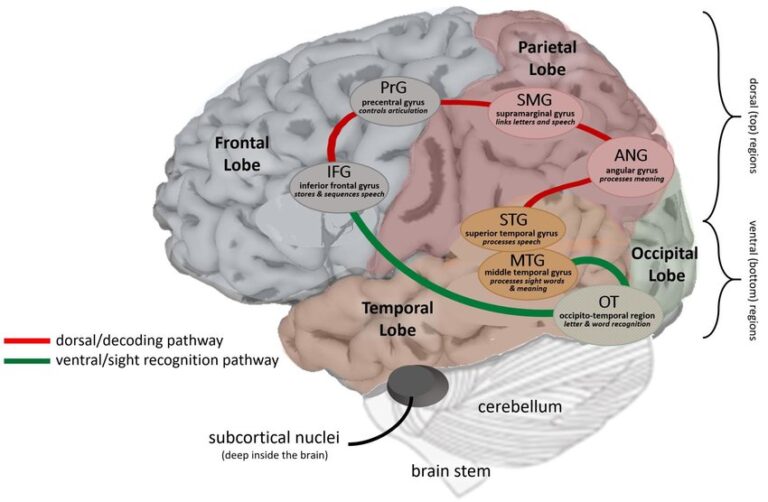

Супрамаргинальная извилина: Функции и Исследования